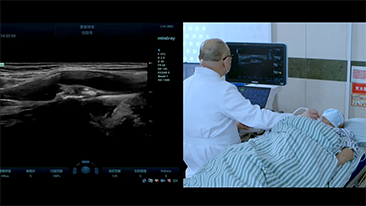

How Clearly Can You See a Liver?

Ultrasound contrast imaging plays a significant role in identifying focal liver lesions, such as hemangioma or liver cancer.

Ultra-wide non-linear UWN+ contrast imaging technology provides better penetration, higher contrast-tissue ratio, with lower MI and longer perfusion time observation.